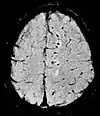

| Diffusion weighted (DWI) | Conventional | DWI | Measure of Brownian motion of water molecules.[17] | High signal within minutes of cerebral infarction (pictured).[18] | ![]() |

Another application of diffusion MRI is diffusion-weighted imaging (DWI). Following an ischemic stroke, DWI is highly sensitive to the changes occurring in the lesion.[44] It is speculated that increases in restriction (barriers) to water diffusion, as a result of cytotoxic edema (cellular swelling), is responsible for the increase in signal on a DWI scan. The DWI enhancement appears within 5–10 minutes of the onset of stroke symptoms (as compared to computed tomography, which often does not detect changes of acute infarct for up to 4–6 hours) and remains for up to two weeks. Coupled with imaging of cerebral perfusion, researchers can highlight regions of "perfusion/diffusion mismatch" that may indicate regions capable of salvage by reperfusion therapy.